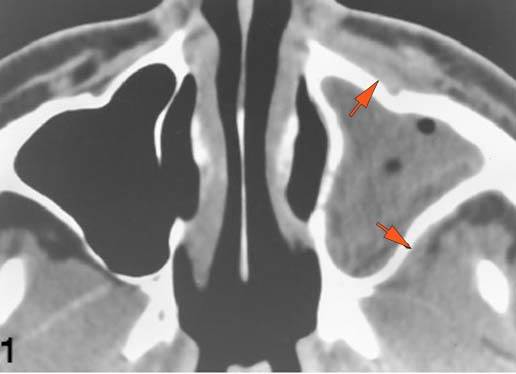

There is infiltration of the fat surrounding the nasolacrimal sac.

There is soft tissue infiltration or bone erosion along the nasolacrimal fossa or canal.